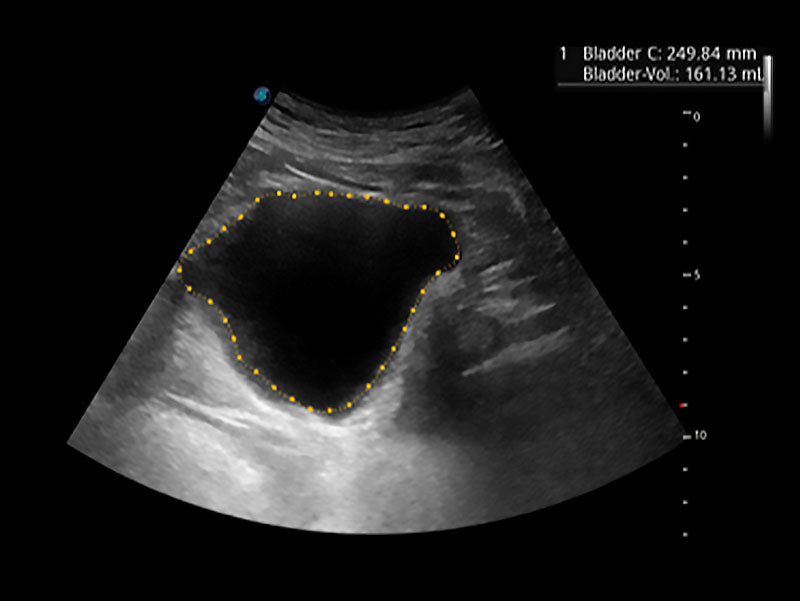

自動化工具

• Auto Bladder 膀胱自動測量

一鍵自動識別膀胱壁及自動測量膀胱容積,不受膀胱形狀和大小的限制,幫助醫(yī)生快速精準(zhǔn)獲得測量的數(shù)據(jù)。